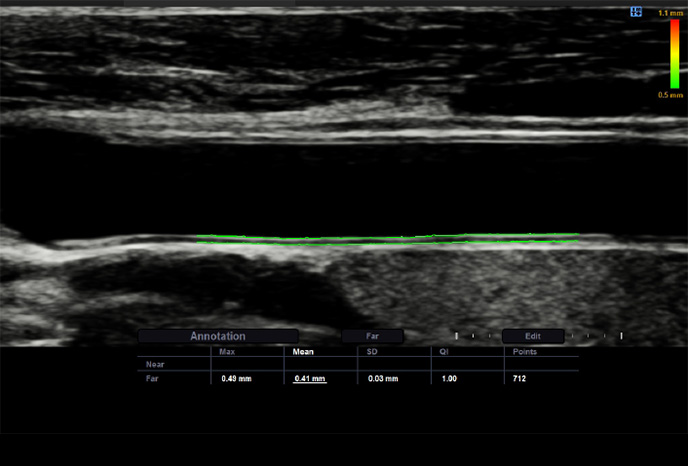

AutoIMT+

AutoIMT + je screeningový nástroj pro analýzu potenciálního rizika kardiovaskulárních onemocnění u pacientů. Umožňuje snadné měření tloušťky intima-media přední i zadní stěny karotidy jedním kliknutím.